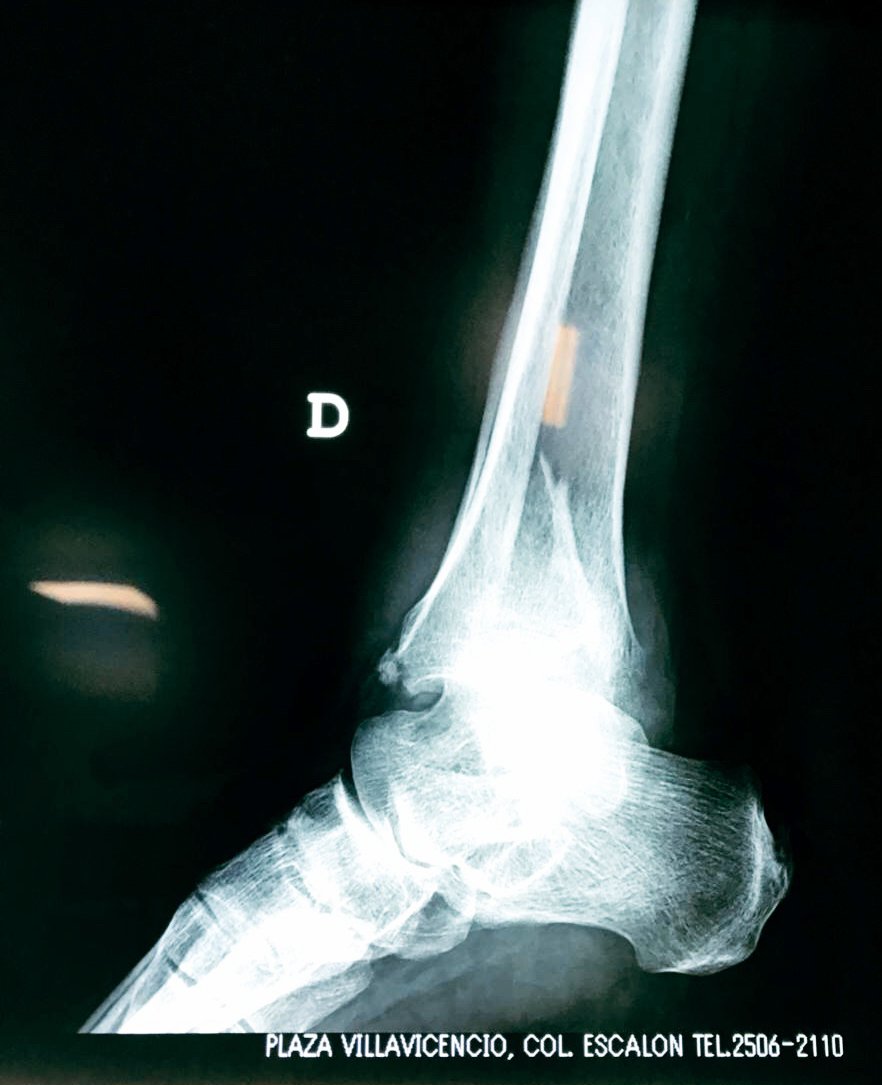

- Los extremos de los huesos están desalineados entre sí (desplazados).

- La fractura se extiende hasta la articulación del tobillo (fractura intra-articular).

- Los tendones o ligamentos (tejidos que sujetan los músculos y los huesos entre sí) están rotos.